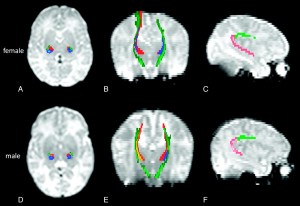

Several studies attempted to answer this question. Although there is a strong body of evidence indicating that females do have an advantage over males in first language acquisition, (Burman, Bitman, & Booth, 2008; Roulstong & Northstone, 2002), not much is known about gender differences in foreign language learning. As Callaghan (1998) and other researchers have noted, there is some evidence of brain lateralization in boys (the belief boys tend to use one hemisphere when processing language processing whereas girls tend to use both). There also seem to be differences in the high cortical functions of the female brain which would facilitate language processing. However, there is no conclusive evidence for either claim.

The findings above point to important affective factors which can be powerful inhibitors of motivation. I do not discount physiological differences in the language-processing of females, as brain imaging has indeed identified greater activity in both cerebral hemispheres in females whilst processing language . This is a very important finding in that implies that females can recruit more support from areas of the brain that boys cannot access during L2 performance.